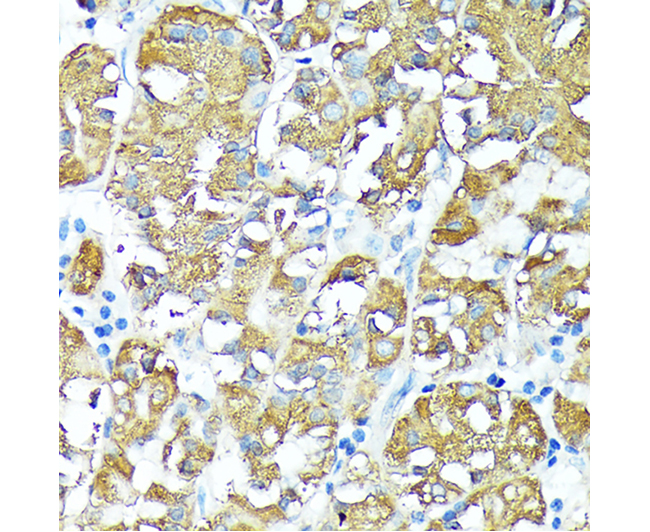

| Fig. 1. Western blot analysis of extracts of various cell lines, using TNFR1 antibody at 1:3000 dilution. Secondary antibody: HRP-labeled Goat Anti-Rabbit IgG(H+L) (A0208) at 1:1000 dilution. Lysates/proteins: 25µg per lane. Blocking buffer: QuickBlock™ Blocking Buffer (P0231). Detection: BeyoECL Star (P0018A). Exposure time:1s. | Fig. 2. Immunohistochemistry of paraffin-embedded human stomach using TNFR1 antibody at dilution of 1:100 (40x lens). |

![]() |

| Fig. 3. Immunohistochemistry of paraffin-embedded rat testis using TNFR1 antibody at dilution of 1:100 (40x lens). | Fig. 4. Immunohistochemistry of paraffin-embedded mouse testis using TNFR1 antibody at dilution of 1:100 (40x lens). |